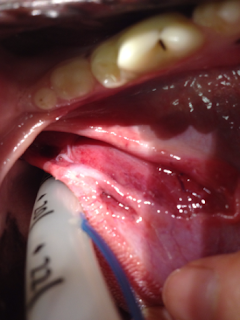

Tongue ripped right up to the tonsil. Wound caused by stick

Splinters and blood removed, wound flushed clean

A zillion tiny stitches in a space my fingers struggle to access